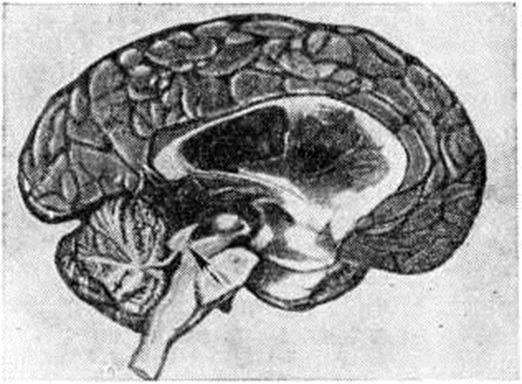

ГидроцефалияГидроцефалия (hydrocephalus; греческий hydor вода + kephale голова; синонимы водянка головного мозга) — состояние, характеризующееся избыточным накоплением цереброспинальной жидкости в желудочках мозга и подоболочечных пространствах. Гидроцефалия является следствием различных заболеваний или травм головного мозга и его оболочек. КлассификацияНаибольшее распространение в СССР получила классификация, предложенная А. А. Арендтом в 1948 год. В ней Гидроцефалия рассматривается в зависимости от времени возникновения, течения, этиологического факторов, локализации и характера нарушения функции ликворного аппарата. По времени возникновения различают врождённую и приобретённую Гидроцефалия, по течению — острую и хроническую. По локализации выделяют наружную и внутреннюю Гидроцефалия При наружной Гидроцефалия имеется избыточное скопление цереброспинальной жидкости преимущественно в субарахноидальных пространствах, при внутренней — в желудочках головного мозга. Нередко наблюдается комбинация внутренней и наружной Гидроцефалия — так называемый общая Гидроцефалия По характеру нарушения функции ликворного аппарата принято различать открытую (сообщающуюся) и закрытую (окклюзионную) Гидроцефалия Открытую Гидроцефалия в свою очередь подразделяют на гиперсекреторную, при которой секреция цереброспинальной жидкости значительно повышена, и арезорбтивную, характеризующуюся нарушением её всасывания. При окклюзионной Гидроцефалия имеется нарушение на различных уровнях оттока цереброспинальной жидкости из желудочков в субарахноидальные пространства в результате спаечного процесса, кист, опухолей и так далее. Встречаются смешанные формы Гидроцефалия, когда окклюзия ликворных путей сочетается с нарушением резорбции или секреции цереброспинальной жидкости. Этиология и патогенезРазличные поражения головного мозга и его оболочек могут привести к Гидроцефалия Чаще всего она наблюдается после инфекционных заболеваний (гнойный эпидемический цереброспинальный менингит, вторичные менингиты и менингоэнцефалиты) и черепно-мозговых травм. Кроме того, Гидроцефалия может возникнуть при затруднении оттока крови из полости черепа (патология венозной системы, тромбоз синусов, сдавление рубцами и спайками отводящих вен), при опухолях, а также при гипертензии, заболеваниях почек и паразитарных поражениях головного мозга. Иногда Гидроцефалия возникает в результате аномалии развития головного и спинного мозга (недоразвитие мозга, мозговые и спинномозговые грыжи и так далее). Вышеперечисленные причины могут привести к нарушению секреции, всасывания или циркуляции цереброспинальной жидкости с последующим развитием Гидроцефалия Патологическая анатомияМорфологически изменения в мозге и оболочках при Гидроцефалия зависят как от основного заболевания, приведшего к Гидроцефалия, так и от длительности повышенного внутричерепного давления. Как правило, наблюдается расширение полостей желудочков, особенно боковых, за счёт увеличения в них количества цереброспинальной жидкости (рисунок 1). Боковые желудочки расширены симметрично как при открытой, так и закрытой Гидроцефалия с окклюзией межжелудочковых отверстий водопровода мозга и апертур IV желудочка (рисунок 2—4). |

Асимметричное расширение желудочков чаще всего наблюдается при закупорке одного межжелудочкового отверстия или на стороне травмы. Прогрессирующее увеличение желудочков приводит к атрофии мозговой ткани, уплощению извилин и сглаживанию борозд мозга. Рано поражаются пирамидные пути. Изменению подвергается прежде всего белое вещество, мозолистое тело и свод. Изменение серого вещества наблюдается при Гидроцефалия в результате травмы и в тяжёлых случаях Гидроцефалия. При врождённой Гидроцефалия может нарушаться строение коры. Атрофия нервной ткани при Гидроцефалия, по мнению У. Пенфилда и Элвиджа (A. Elwidge, 1932), Б. Н. Клосовского (1949), В. П. Пурина (1968), происходит в результате сдавления капилляров мозга вследствие внутричерепной гипертензии. Выраженная астроцитарная реакция в белом веществе при Гидроцефалия является плохим прогностическим признаком. Кроме изменений со стороны ткани мозга, при Гидроцефалия отмечают выраженные изменения и со стороны сосудистых сплетений, эпендимы желудочков и его оболочек. Наблюдается атрофия сосудистых сплетений с фиброзным перерождением их соединительнотканной основы и гибелью эпителия. При Гидроцефалия после инфекционных заболеваний выявляют признаки гранулематозного эпендиматита (смотри Хориоэпендиматит). Мозговые оболочки резко утолщены, мутны, отёчны. Отмечают их фиброз, сращение главным образом в области базальных цистерн основания мозга, большого затылочного отверстия и апертур IV желудочка. В оболочках выявляют воспалительные инфильтраты. При травматической Гидроцефалия в мозге находят следы бывших кровоизлияний, рубцы в местах некрозов мозговой ткани, спайки в области путей оттока цереброспинальной жидкости и так далее. В сосудах головного мозга при Гидроцефалия обнаруживают признаки артериосклероза с гиалинозом сосудов.

Рисунок 5. | ||